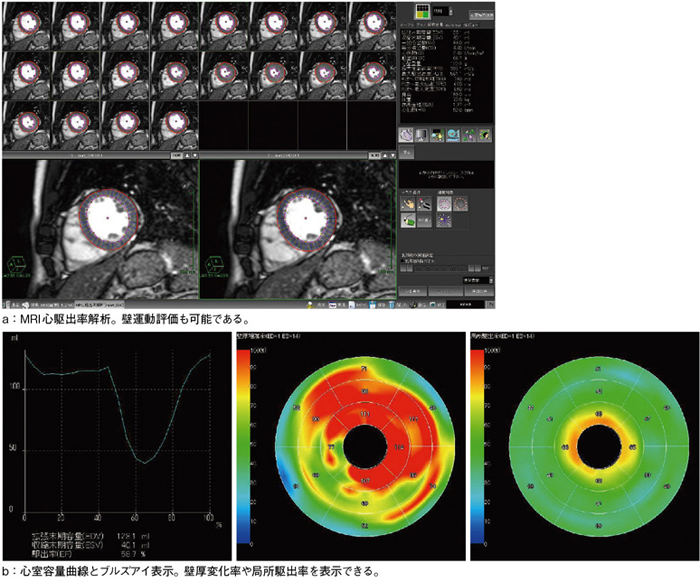

頭部造影CT | 兵庫県立加古川医療センター, 当院におけるAZE VirtualPlaceの使用経験ーMRI心臓検査を中心に

当院におけるAZE VirtualPlaceの使用経験ーMRI心臓検査を中心に